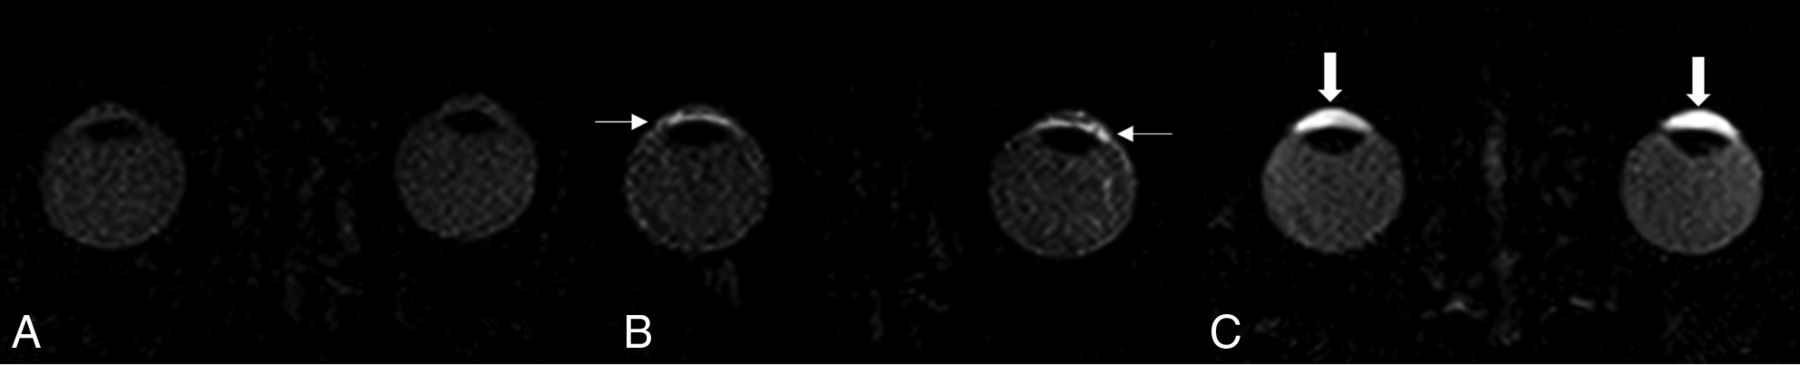

Image demonstrating contrast agent kinetics after injection of gadolinium in healthy patients: native scan (A), scan 20 minutes after Gd injection demonstrating the physiologic permeability of Gd in the lateral eye chamber (small arrow) (B), and physiologic, symmetric enhancement in the central eye chamber and the VB in the late scan after 120 minutes (C) (thick arrows).